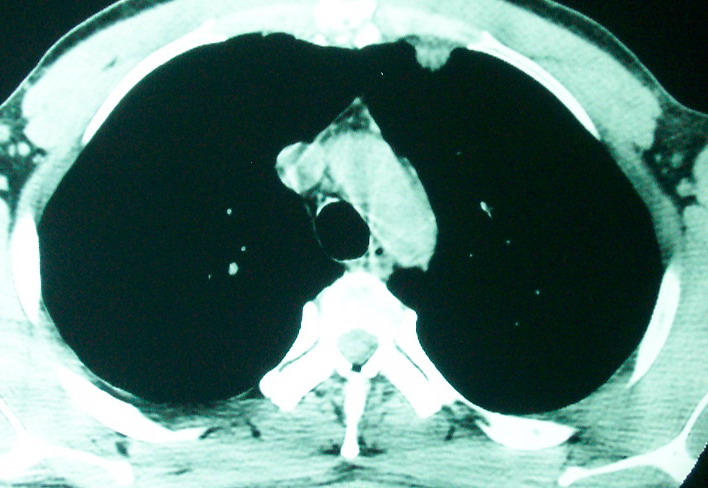

m      37y      发热   咳脓痰月余      ct肺脓肿但住院抗炎治疗后双肺内结节不知该如何解释

治疗后见左肺下野病灶较前缩小但双肺内结节影似无变化请较各位老师该如何下结论    治疗前wbc14.5 治疗后wbc 11.0

如果你仔细的同层面对比,你会发现所有的病灶均有比较明显的吸收、缩小。病变的形态,特别是脓肿的形态、壁的厚薄、内壁均有很大的变化,均在往好的方面发展。与临床症状、血像均符合,治疗效果比较显著,就是肺脓肿并双肺的化脓性炎症灶。